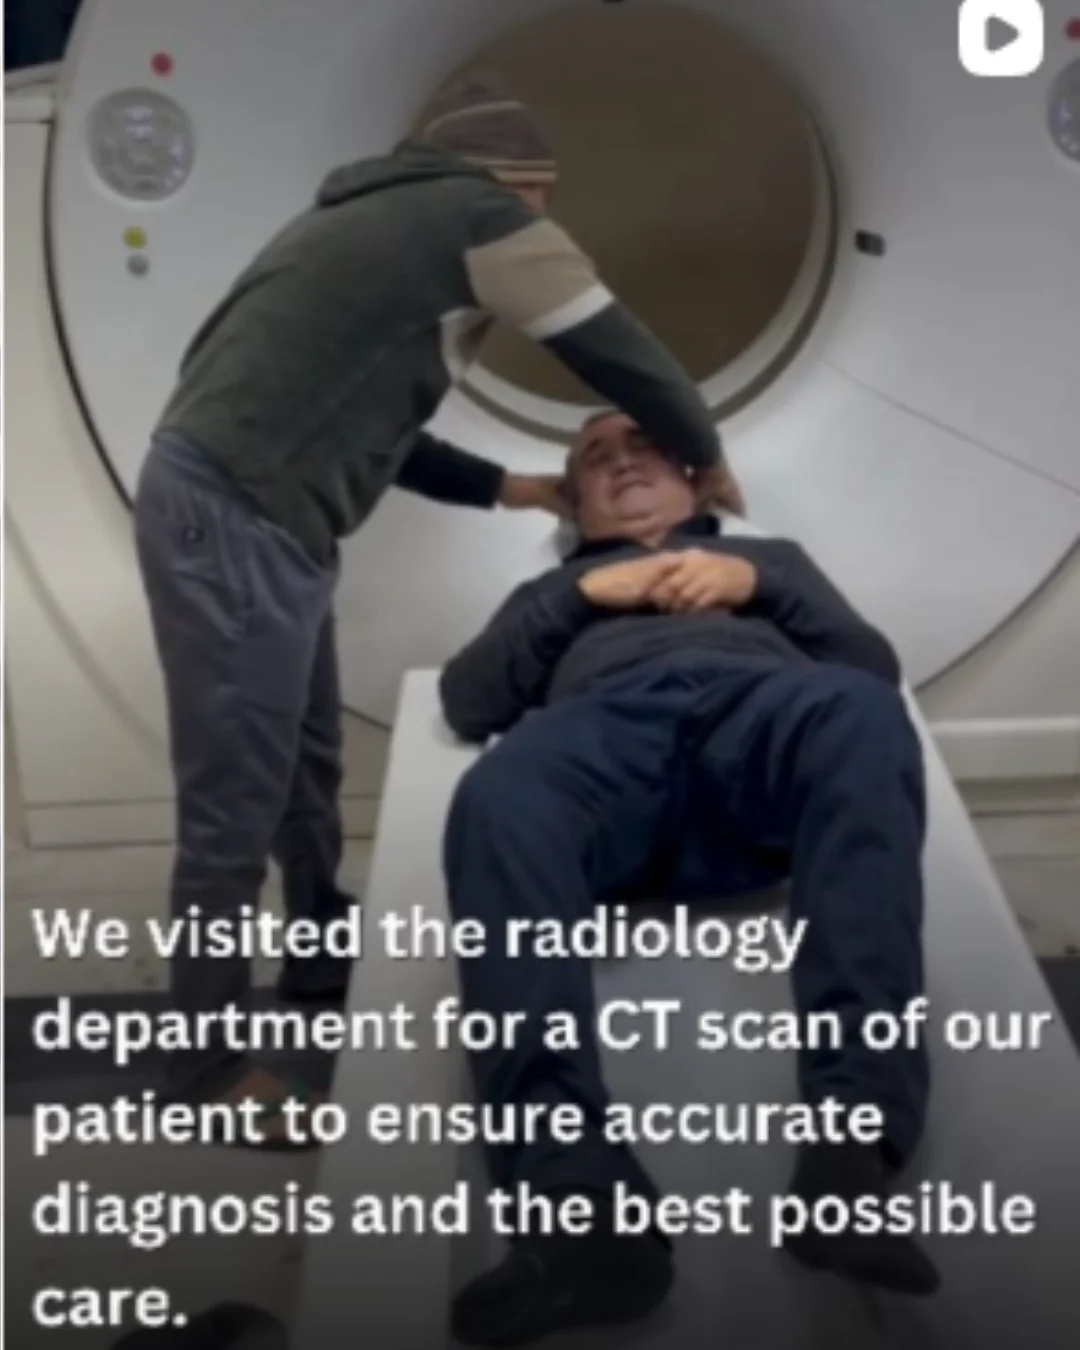

Healthcare Treatment & Medical Travel Support

CURETAKE is not an online store and does not sell products. We provide guidance and coordination for medical treatments by connecting patients with trusted hospitals and experienced doctors in India.

Every patient’s medical need is unique. Instead of fixed pricing or products, we focus on understanding medical reports, treatment requirements, and patient preferences to help identify the most suitable care options.

Effective medical planning requires clarity, communication, and coordination. That is why CURETAKE works closely with patients, doctors, and hospitals to ensure transparent information, realistic treatment expectations, and structured care planning.

Healthcare decisions are not made in isolation. Treatment outcomes depend on expert evaluation, hospital infrastructure, and personalized care. Our role is to support patients at every stage — from initial inquiry and cost estimation to treatment coordination and recovery assistance.